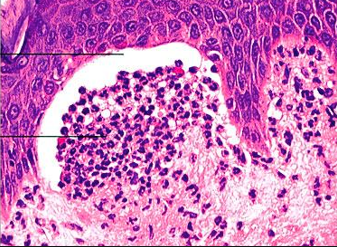

What is most likely the etiology of the malabsoption disorder in this person?

• Key features?

Etiology is most likely Celiac Disease - seen here are many intravillus lymphocytes (seeing one or two is normal, but this may is pathologic)

**This is more important the villus blunting when you’re trying to make a diagnosis of celiac disease